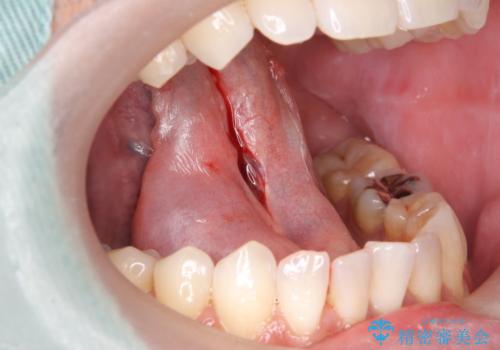

- 舌を動かしにくいとのことで来院されました。

舌の裏側にある舌小帯という部分が短い状態だったため、舌小帯の切除をすることとなりました。